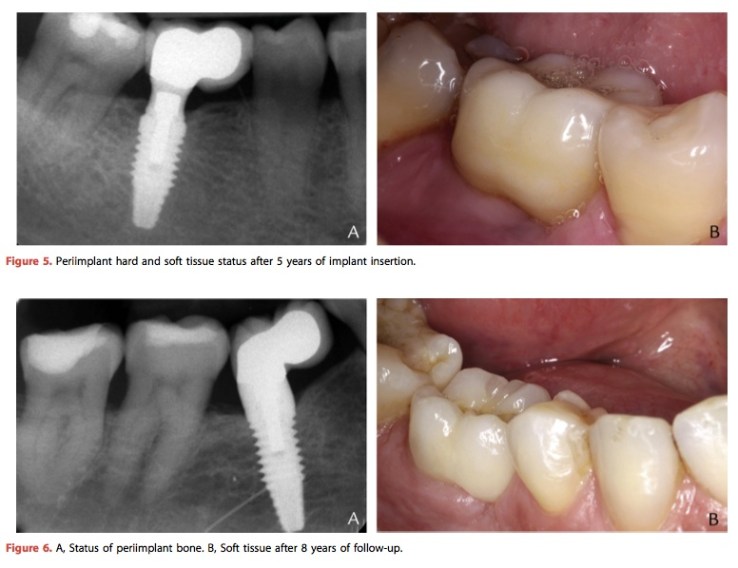

這篇文章中在31位患者上共有34支植體, 然後都是種植在偏遠心側的位置. 平均追蹤4年, 植體存活率為97.1%(失敗一支). 近遠心的骨質損失並無統計上差異.所以如果真的在正中心的骨質不好, 可以稍微偏近心或是遠心種, 畢竟自己好的骨頭還是比GBR的好.